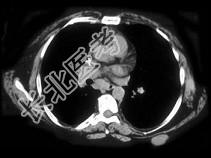

- 单项选择题根据皮下组织的表现,该病例可能性最大的诊断为 ( )

A、转移

B、淋巴瘤

C、良性囊肿

D、黑色素瘤

E、纤维瘤